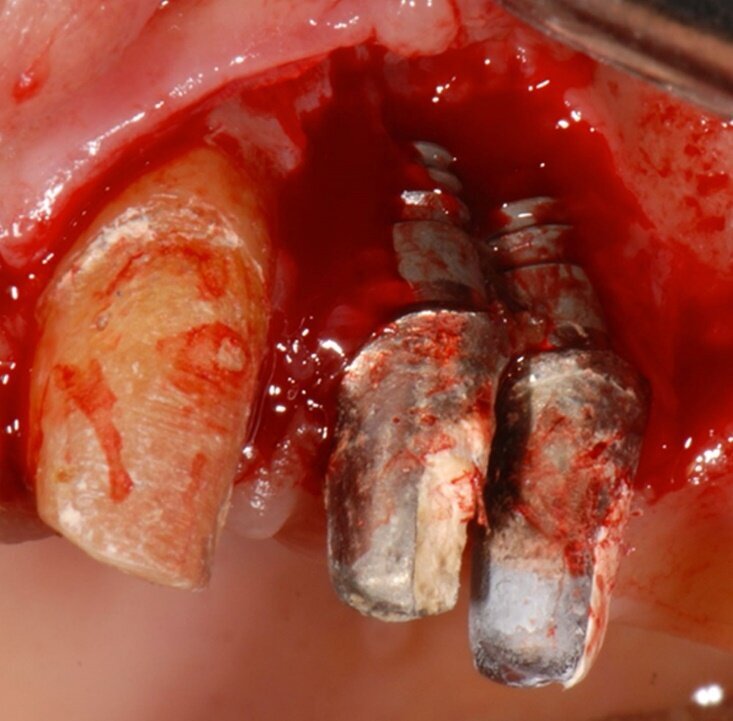

Fig. 2 - Aspetto dei due impianti alla chirurgia di rimozione implantare; si noti come il riassorbimento osseo giunge al livello apicale degli impianti.